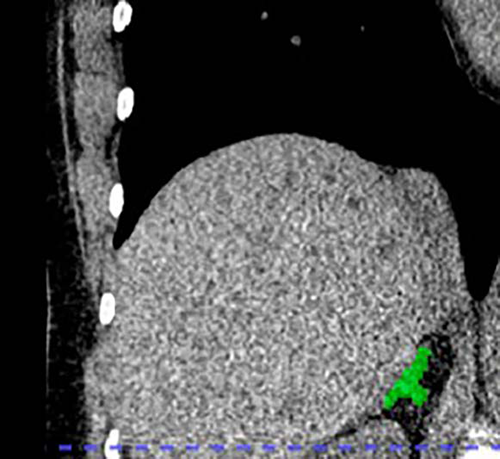

Figure 4. Left adrenal automated 2D segmentation in chest CT.